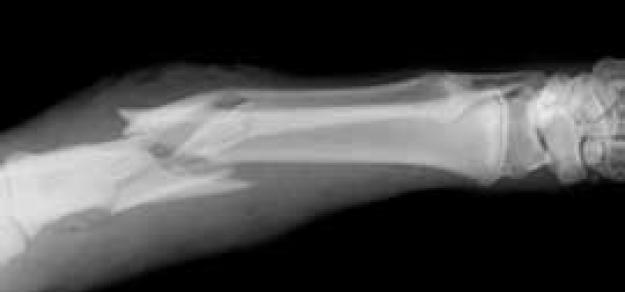

Diabetes, tratamiento y riesgo de fractura

14 febrero 2019

El control glucémico más estricto se asoció con menor riesgo de fracturas en pacientes con diabetes tipo 1 pero no en diabetes tipo 2. Los usuarios de glitazonas tuvieron un riesgo aumentado. Journal of Clinical Endocrinology & Metabolism, 16 de enero de 2019